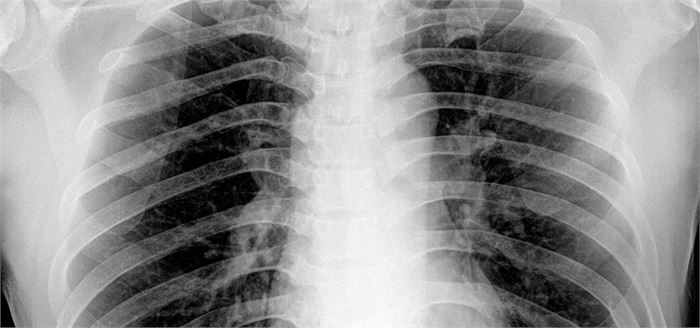

Pneumonia happens due to the inflammation of the lung tissues which occurs primarily because of an infection. Pneumonia is way more serious than bronchitis, and when the two happen together, the condition is called bronchopneumonia.

If you were already in poor health or are old or a chronic patient, then it is safer to get treatment in the hospital. Often patients are made to go through certain tests such as Blood tests, sputum tests and also chest x rays. In really severe cases, patients might require oxygen and other supportive treatments.

(Featured Image Courtesy: The Indian Express)